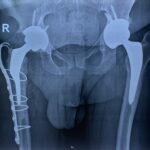

7. Πάσχω από σοβαρή αρθρίτιδα και στα δύο Ισχία. Μπορώ να χειρουργηθώ και στα δύο ισχία ταυτόχρονα;

Ο συνδυασμός της ελαχιστοποίησης του τραύματος (με όλα τα πλεονεκτήματα που προαναφέρθηκαν) και της ύπτιας θέσης του ασθενούς στο χειρουργείο, στο τραπέζι έλξης, διευκολύνει την επιλογή αυτή. Στην κλινική μας έχουμε πραγματοποιήσει σημαντικό αριθμό αρθροπλαστικών “δύο επεμβάσεις – μία αναισθησία”. Θα σας προτείνουμε την επιλογή αυτή αν η γενική υγεία σας το επιτρέπει, με κύριο μέλημα την ασφάλειά σας.

Στην εικόνα 6 βλέπουμε την προεγχειρητική ακτινογραφία άνδρα 56 ετών που υποβλήθηκε σε ταυτόχρονη αρθροπλαστική AMIS με navigation robotic assistance. Στην εικόνα 21 ο προεγχειρητικός τρισδιάστατος σχεδιασμός, αναλυτικά. Στην εικόνα 22 η πλοήγηση από το σύστημα διεγχειρητικά, με απόλυτη ακρίβεια και το άριστο τελικό ακτινολογικό αποτέλεσμα. Ο ίδιος ασθενής στην επανεξέταση, 24 μέρες μετά την επέμβαση στο ιατρείο.